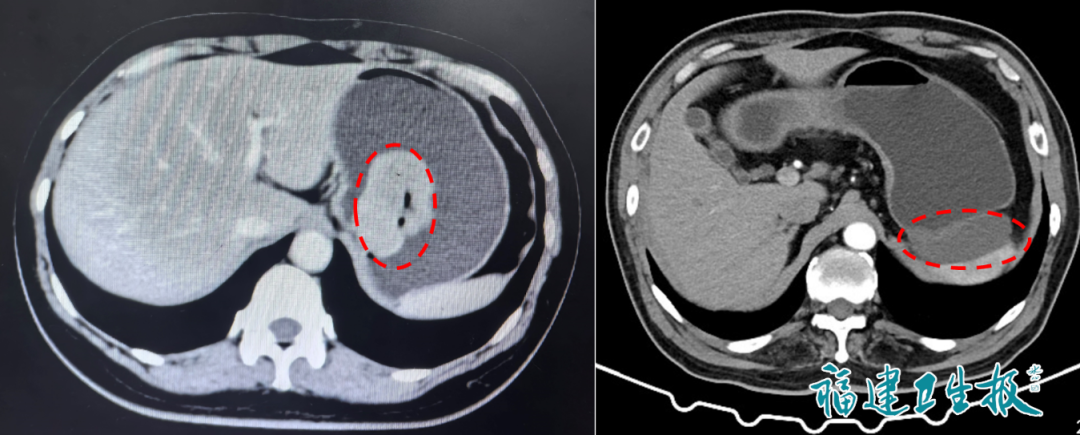

▲胃肠道间质瘤的CT表现(左:内生型;右:外生型)